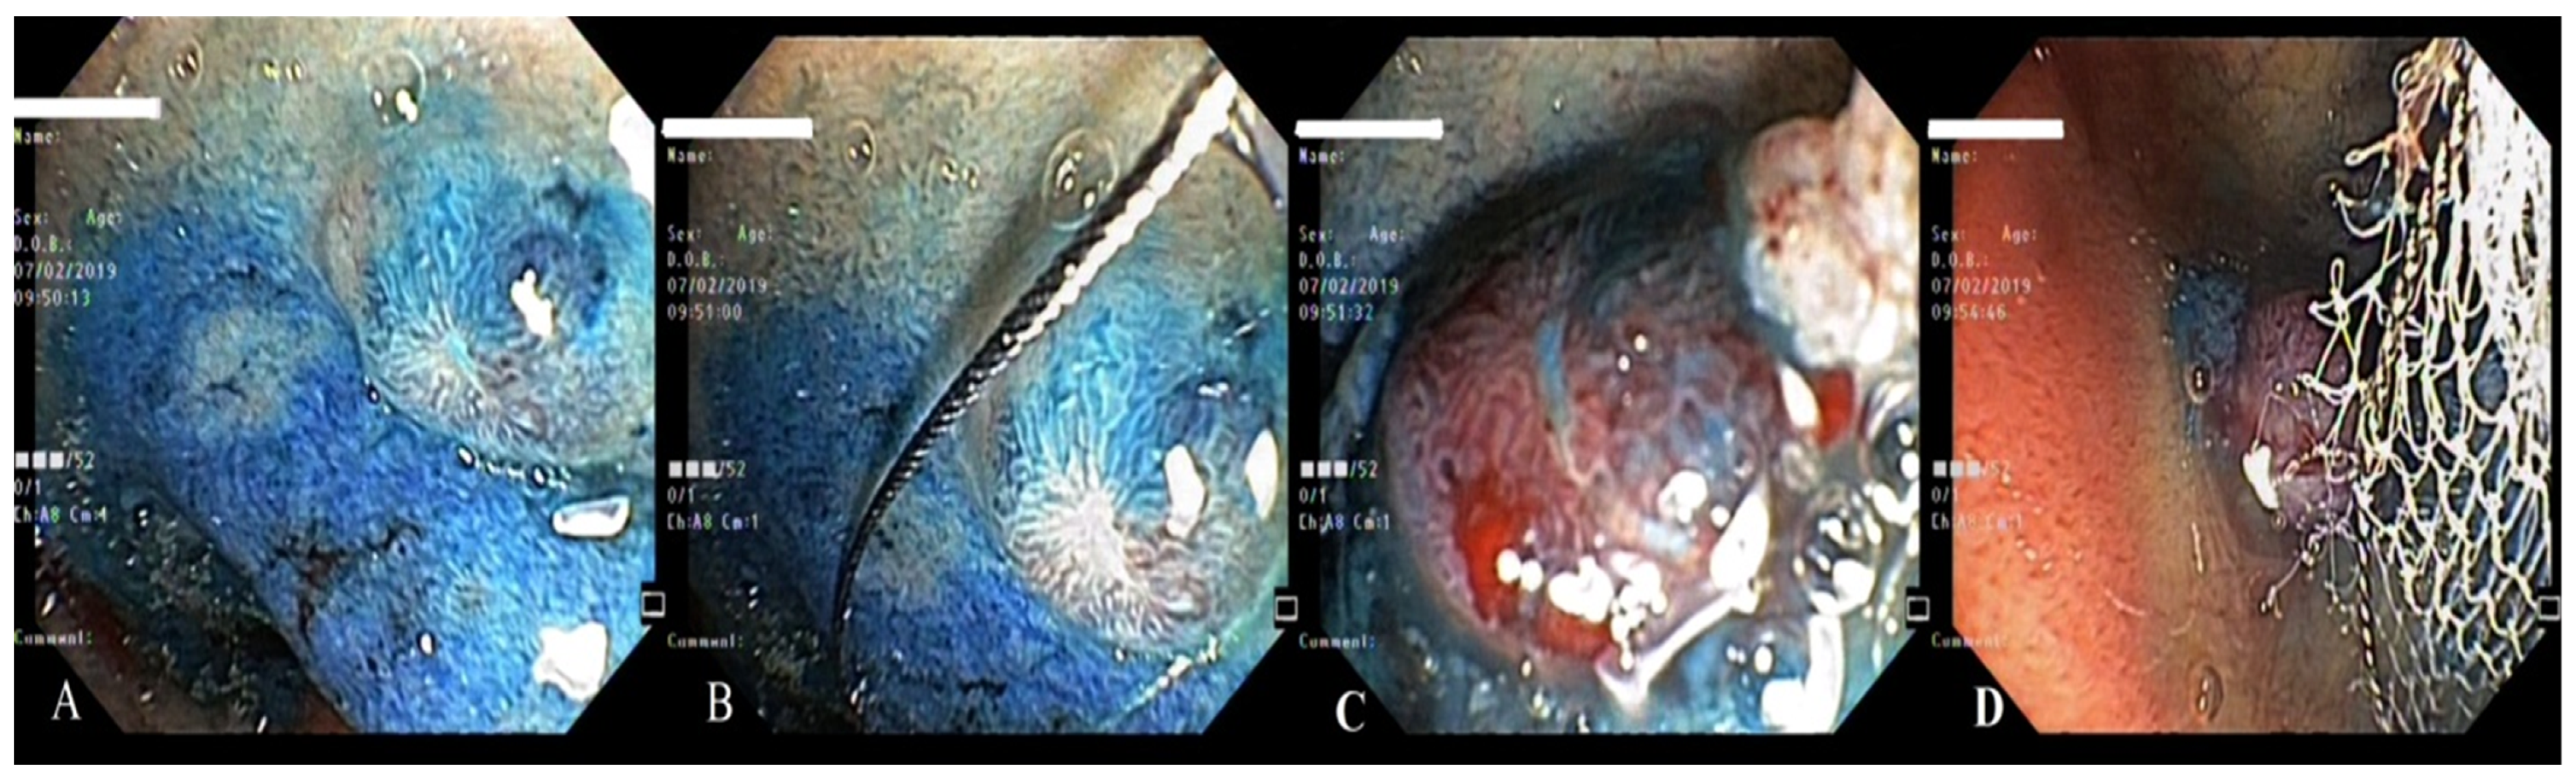

3. Case Report 2